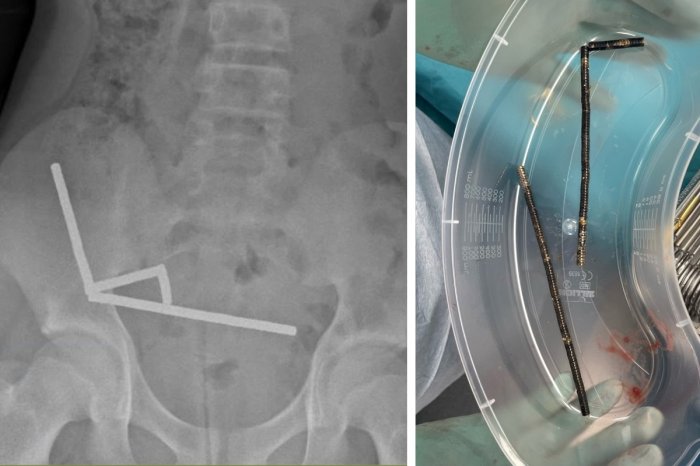

Röntgenové snímky odhalili, že magnety sa v chlapcovom tele pospájali a v čreve vytvorili štyri reťazce. Magnety tlačili na stenu čreva a jeho časť už podliehala nekróze.

Chirurgom sa podarilo magnety odstrániť, no chlapec prišiel o časť čreva. Podľa zverejnenej správy sa tínedžer po operácii zotavil a po 8 dňoch bol prepustený z nemocnice.